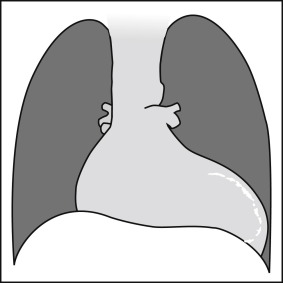

Graphic 17-1

Posteroanterior projection: calcified left ventricular aneurysm. Note a thin and well-defined line of calcification toward the left ventricular apex/free wall, as well as cardiomegaly.